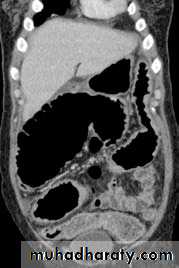

Advanced esophageal Ca